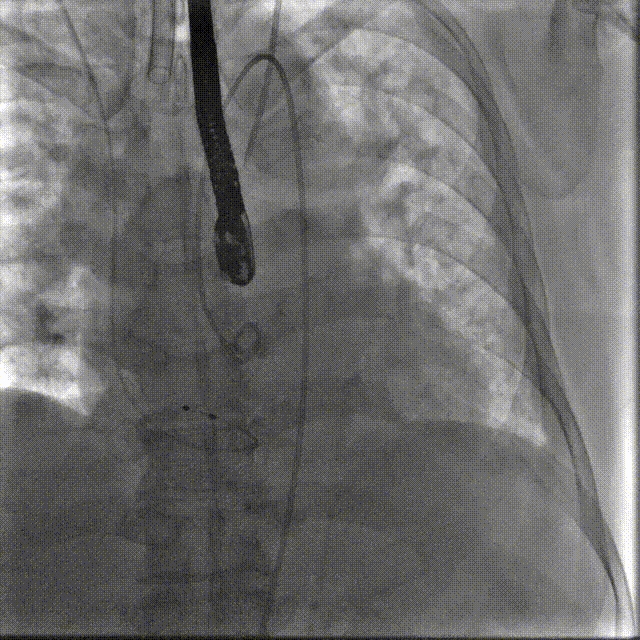

手术过程概览

置入猪尾进行根部造影,造影可见根部钙化不均匀,瓣叶活动度低,冠脉灌注良好。

根部造影

22mm球囊预扩,轻微腰征,冠脉显影良好,无造影剂渗漏。

22mm球囊预扩

TaurusElite AV29号瓣膜定位及释放。瓣膜初始定位-3位,开花后120次起搏,释放到工作位后造影显示锚定充足,位置良好,冠脉未见遮挡,继续缓慢旋转手柄,轻推输送器,瓣膜逐一脱钩,顺利释放。

瓣膜初始定位

瓣膜释放过程

工作位造影

瓣膜脱钩

释放后多体位观察造影,提示瓣膜位置良好,展开良好,双侧冠脉未见遮挡,微量瓣周漏。

最终造影

术前跨瓣压差70mmHg

术后跨瓣压差1mmHg